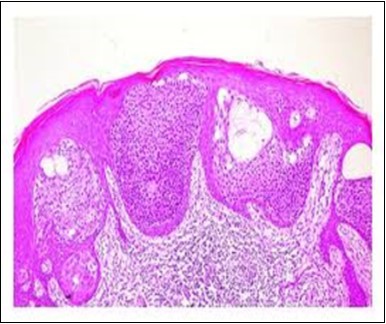

Granular arrangement of malignant cells and intercellular bridges are conspicuous with the demonstration of nuclear atypia, pleomorphism, prominent mitosis and tumour necrosis. A peripheral palisade is discernible within the cellular aggregates. Mitotic figures are common and can be quantified as up to 12 mitosis/ high power field. Tumour differentiation can prominently be of the ductal category with the demonstration of intra-cytoplasmic lumina. Comedo type tumour necrosis is evident along with foci of squamous differentiation The neoplasm is reactive to periodic acid Schiff ‘s (PAS) stain. (Figure 1, Figure 2, Figure 3, Figure 4, Figure 5, Figure 6, Figure 7, Figure 8, Figure 9, Figure 10, Figure 11, Figure 12, Figure 13.

Figure 5.Sweat glandular articulations and malignant cellular aggregates with cystic spaces in eccrine porocarcinoma(17).